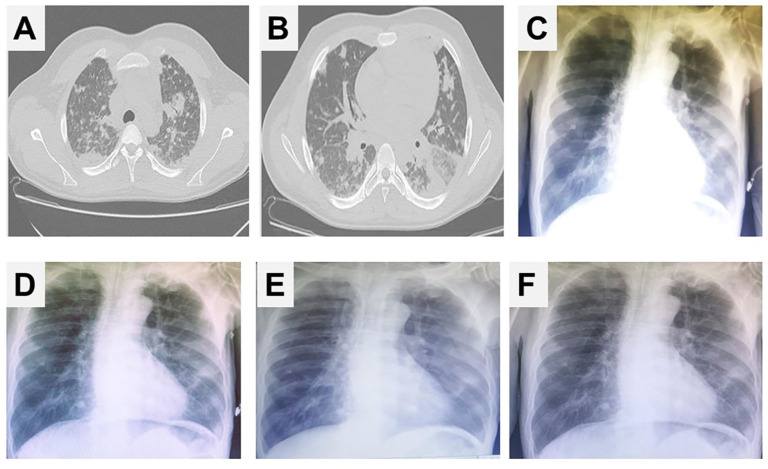

Inhalation of methanol vapor is a rare but potentially life-threatening occupational hazard, particularly in environments with inadequate ventilation and safety controls. We report the case of an 18-year-old male shrimp processing worker who developed acute respiratory failure following accidental inhalation of methanol vapors mislabeled as kerosene. The patient presented with severe dyspnea, hypoxemia, metabolic acidosis, and radiographic findings of diffuse pulmonary infiltrates. He required mechanical ventilation, corticosteroids, antibiotics, and intensive supportive care. Bronchoscopy revealed erythematous bronchial mucosa with hemorrhagic stippling and was followed by bronchoalveolar lavage (BAL). Based on imaging findings, therapeutic segmental pulmonary lavage (TSPL) was performed, targeting the most affected lower lobe segments. The procedure involved instillation and aspiration of small saline aliquots to remove inflammatory debris. Following TSPL, the patient exhibited marked clinical improvement, with normalization of inflammatory markers and successful extubation within 48 hours. This case illustrates the potential value of TSPL as an adjunctive therapy in methanol-induced chemical pneumonitis. Unlike standard BAL, TSPL enables targeted clearance of toxic exudates from specific lung segments, potentially accelerating recovery in patients with localized airway injury. Given the rarity of inhalational methanol poisoning and the absence of established respiratory interventions beyond supportive care, TSPL may offer a novel approach to managing severe pulmonary complications. This experience highlights the need for heightened clinical awareness of inhalational toxic exposures and further research into therapeutic lavage techniques. Our findings suggest that TSPL could be considered in selected cases of toxic inhalation injury when conventional measures fail to produce timely improvement.